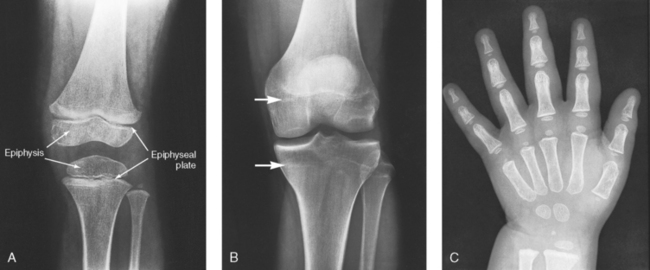

Secondary ossification occurs after birth when a separate bone begins to develop at both ends of each long bone. Each end is called the epiphysis (Fig. 3-15, B). At first, the diaphysis and epiphysis are distinctly separate. As growth occurs, a plate of cartilage called the epiphyseal plate develops between the two areas (Fig. 3-15, C). This plate is seen on long bone radiographs of all pediatric patients (Fig. 3-16, A). The epiphyseal plate is important radiographically because it is a common site of fractures in pediatric patients. Near age 21 years, full ossification occurs, and the two areas become completely joined; only a moderately visible epiphyseal line appears on the bone (Fig. 3-16, B).

Fig. 3-16 A, Radiograph of a 6-year-old child. Epiphysis and epiphyseal plate shown on knee radiograph (arrows). B, Radiograph of same area in a 21-year-old adult. Full ossification has occurred, and only subtle epiphyseal lines are seen (arrows). C, PA radiograph of hand of a 2½-year-old child. Note early stages of ossification in epiphyses at proximal ends of phalanges and first metacarpal, distal ends of other metacarpals, and radius. (C, From Standring S: Gray’s anatomy, ed 40, New York, 2009, Churchill Livingstone.) Churchill Livingstone